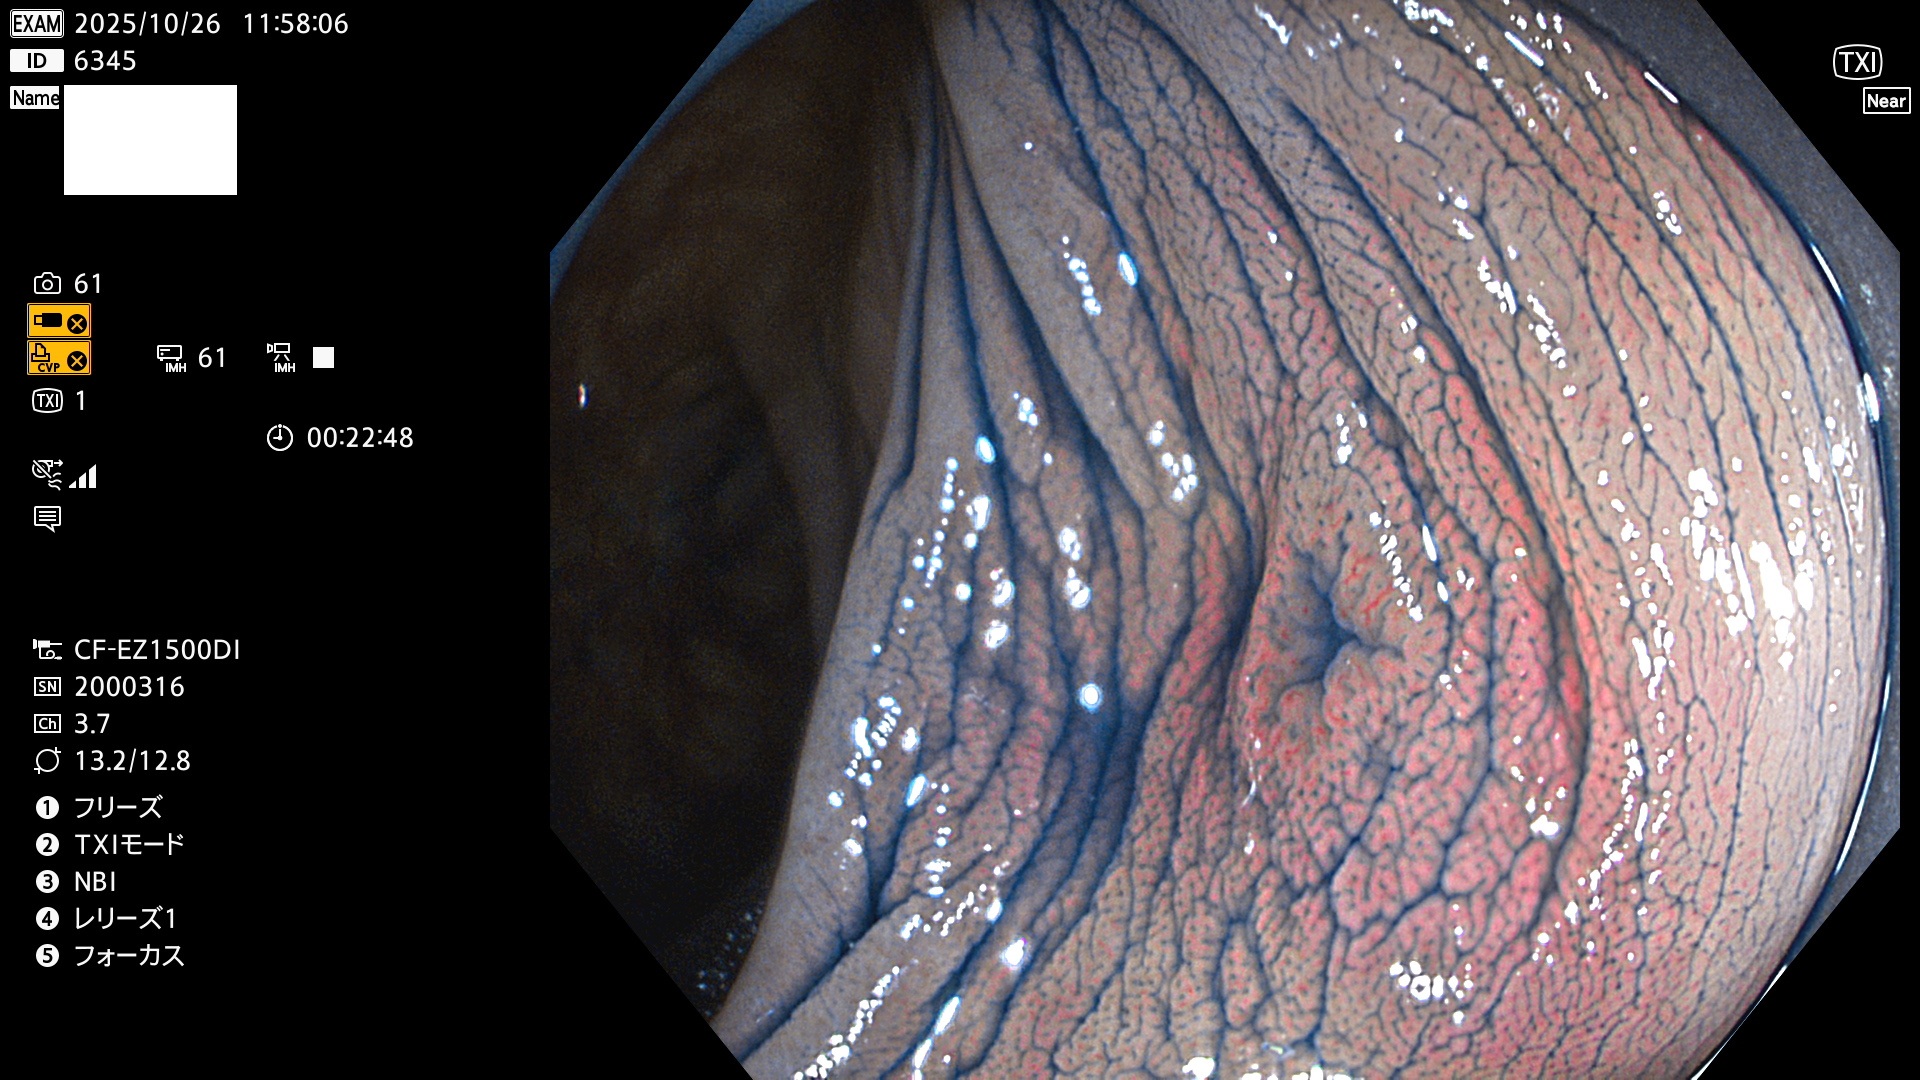

完全に平坦な物をUb、陥凹している物をUcと呼びます。Ubは認識が困難で、Ucはびらん(炎症)と紛らわしいために見落とされやすく、「内視鏡後・大腸癌」の原因になります。

毎週の検査(木・金・土・日)に発見されたUbとUc型・腺腫を、その週の日曜の夜にUPし1週間、提示します。

2025年10月23日〜10月26日の4日間(40件)で6個 (Uc_ADR=6個/40人=15%)